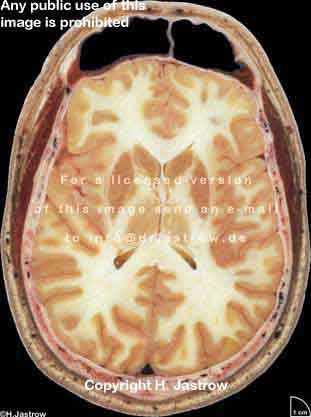

??? ! § ! Copyright H. Jastrow

Visible Human male: Sectio transversalis 1084